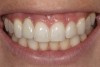

Fig 1. Midfacial recession can affect the esthetics of a smile and lead to an unsatisfactory outcome.

Fig 3. A patient presented with a high smile line and midfacial recession of the maxillary right lateral incisor as evidenced by the increased tooth length compared with the contralateral lateral incisor.

Problem: The implant is placed too facial with significant recession on the midfacial aspect of the abutment and/or crown; the implant is healthy and the patient has a high smile line with an intermediate to thick periodontal phenotype (Figure 1 and Figure 2).17-19

The following case report provides an example of this case scenario: A 28-year-old white female patient presented with her maxillary right lateral incisor significantly longer than the contralateral tooth following restoration of an existing crown that was 10 years old (Figure 3). The patient was dissatisfied with the esthetic appearance of the restoration due to the increased length, recession of the gingival tissues, and discoloration of the surrounding mucosa (Figure 4). Similar to case scenario No. 1, the first step in treatment was to decoronate the healthy implant by placing a flat surgical cover screw and employing a provisional resin-bonded-retained (RBR) prosthesis as a transitional fixed restoration (Figure 5 and Figure 6). The gingival augmentation in situ was allowed to take place for 2 to 3 weeks and was evaluated after that time (Figure 7).